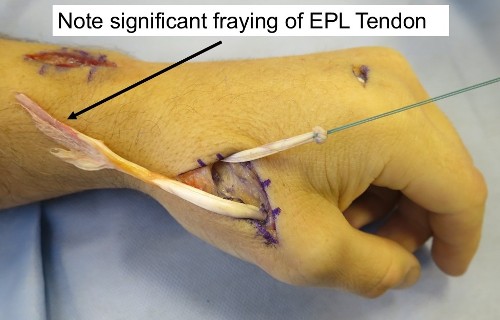

1. Repair of the tendon is not possible – The tendon is often frayed over a considerable distance before it eventually ruptures